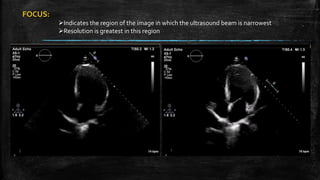

FOCUS:

Indicates the region of the image in which the ultrasound beam is narrowest

Resolution is greatest in this region